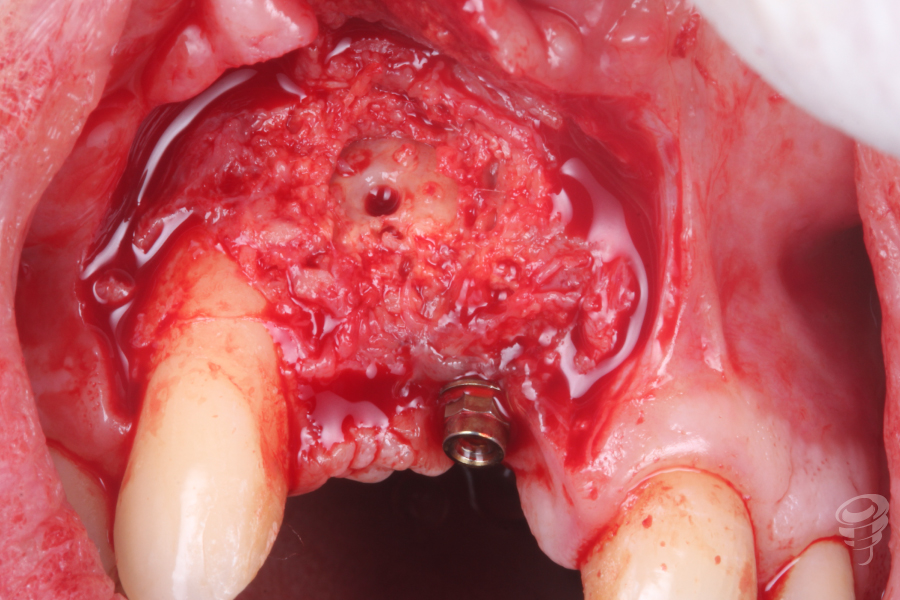

Colocamos un tornillo de Tent Pole en la zona del defecto creado por el implante en 12 para conseguir un relleno óseo adecuado.

Imagen 5

Imagen 6

Una vez estabilizado el tornillo Tent Pole, manteniendo la distancia al hueso remanente, procedemos a rellenar con hueso autólogo de fresado y xenoinjerto. Posteriormente colocamos una membrana de colágeno fijada con chinchetas. (Imagen 7 y 8). Finalmente procedemos a realizar la sutura.